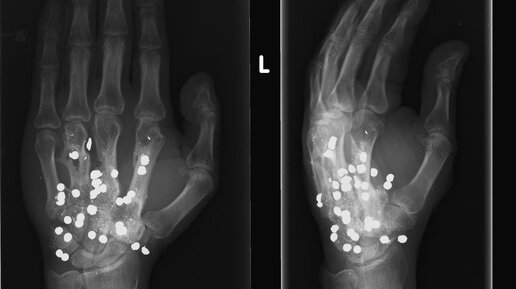

Необычные рентгеновские снимки

Представляем вашему вниманию 10 разных рентгеновских снимка ,которые могут повернуть вас в шок